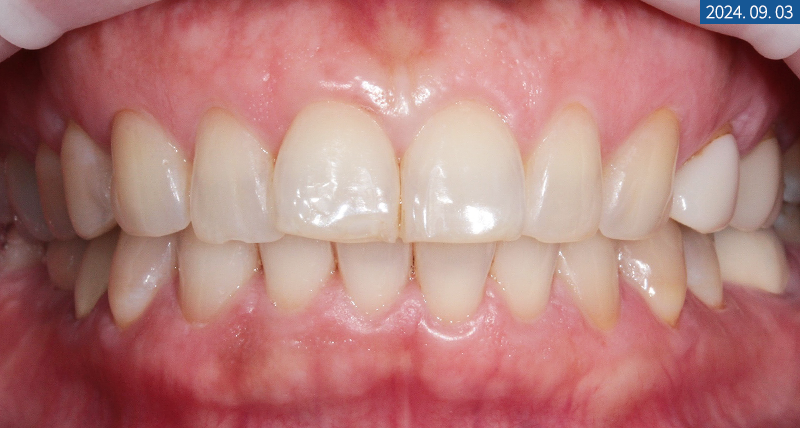

저희 서울센텀치과에 오셔서

라미네이트 상담을 받으신 중년 여성분께서

변색된 치아색을 더 하얗게 바꾸고 싶고

살짝 금 간 부분 때문인지 시려서 불편해요.

라는 이유로 치료를

받아보고 싶다고 하셨습니다.

정확한 구내 파악을 위해

파노라마 엑스레이를 촬영해 보니

어금니 임플란트 식립과 크라운 수복,

신경 치료, 보철물로 때운 곳이 보였습니다.

다행히 라미네이트 받기를 원하시는 전치부에는

미세 크랙 외에 큰 이상 소견이 보이지 않아

도재를 아름답게 부착해 드리기로 했는데요.